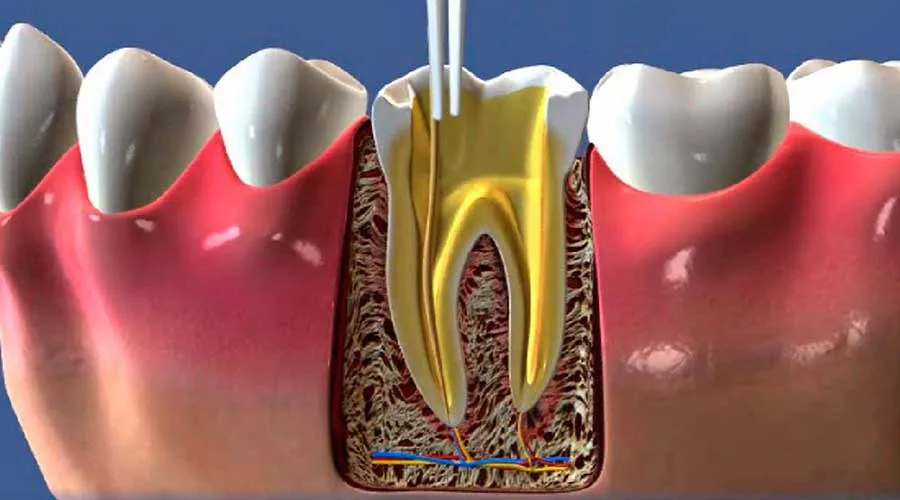

Esta área da odontologia foca especificamente no cuidado da polpa dentária, o tecido interno do dente que contém nervos e vasos sanguíneos.

O uso de tecnologia avançada em um consultório especializado em endodontia é um diferencial que transforma a experiência do paciente, tornando procedimentos complexos muito mais simples e seguros.

O foco desse atendimento é eliminar infecções e inflamações de forma definitiva. Ao tratar a raiz do problema, o especialista restabelece a saúde bucal, fundamentando a longevidade da dentição original e o bem-estar sistêmico do indivíduo em seu cotidiano.

Tecnologia: Uso de microscopia operatória e localizadores apicais para exatidão milimétrica;

Protocolos Rigorosos: Métodos de desinfecção profunda que elevam a taxa de sucesso;

Equipamentos Modernos: Sistemas rotatórios e radiografia digital que agilizam o diagnóstico e a execução;

A utilização de recursos de última geração aumenta a eficácia dos procedimentos, permitindo que tratamentos de canal sejam finalizados com rapidez e precisão.

Preparação e Exames: Realização de imagens digitais para mapear a situação da polpa dentária;